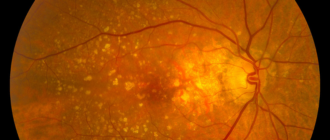

Дистрофия сетчатки глаза: причины, симптомы дегенерации, лечение истончения уколами, каплями и народными средствами Внутренняя